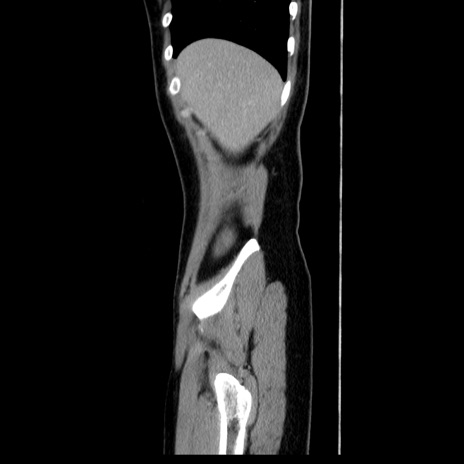

症例39(矢状断像)

【症例】40歳代女性

【主訴】上下腹部痛

【現病歴】2日目から下腹部痛あり。夜間は痛みで眠れなかった。昨日より上腹部痛と下痢が出現。臥位で痛みは軽快したため、休んでいた。本日になって臥位でも立位でも痛みが強くなってきたため救急要請。

【既往歴】子宮内膜症

【身体所見】部:平坦・軟、左上下腹部に圧痛あり、反跳痛あり。

【データ】WBC 21800、CRP 26.78

CT